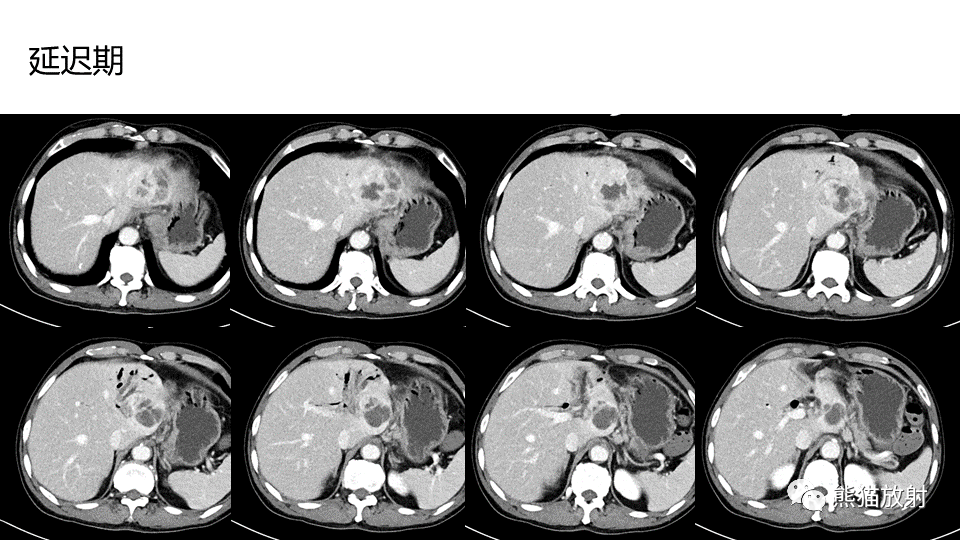

【PPT】肝内胆管细胞癌 VS 肝脓肿